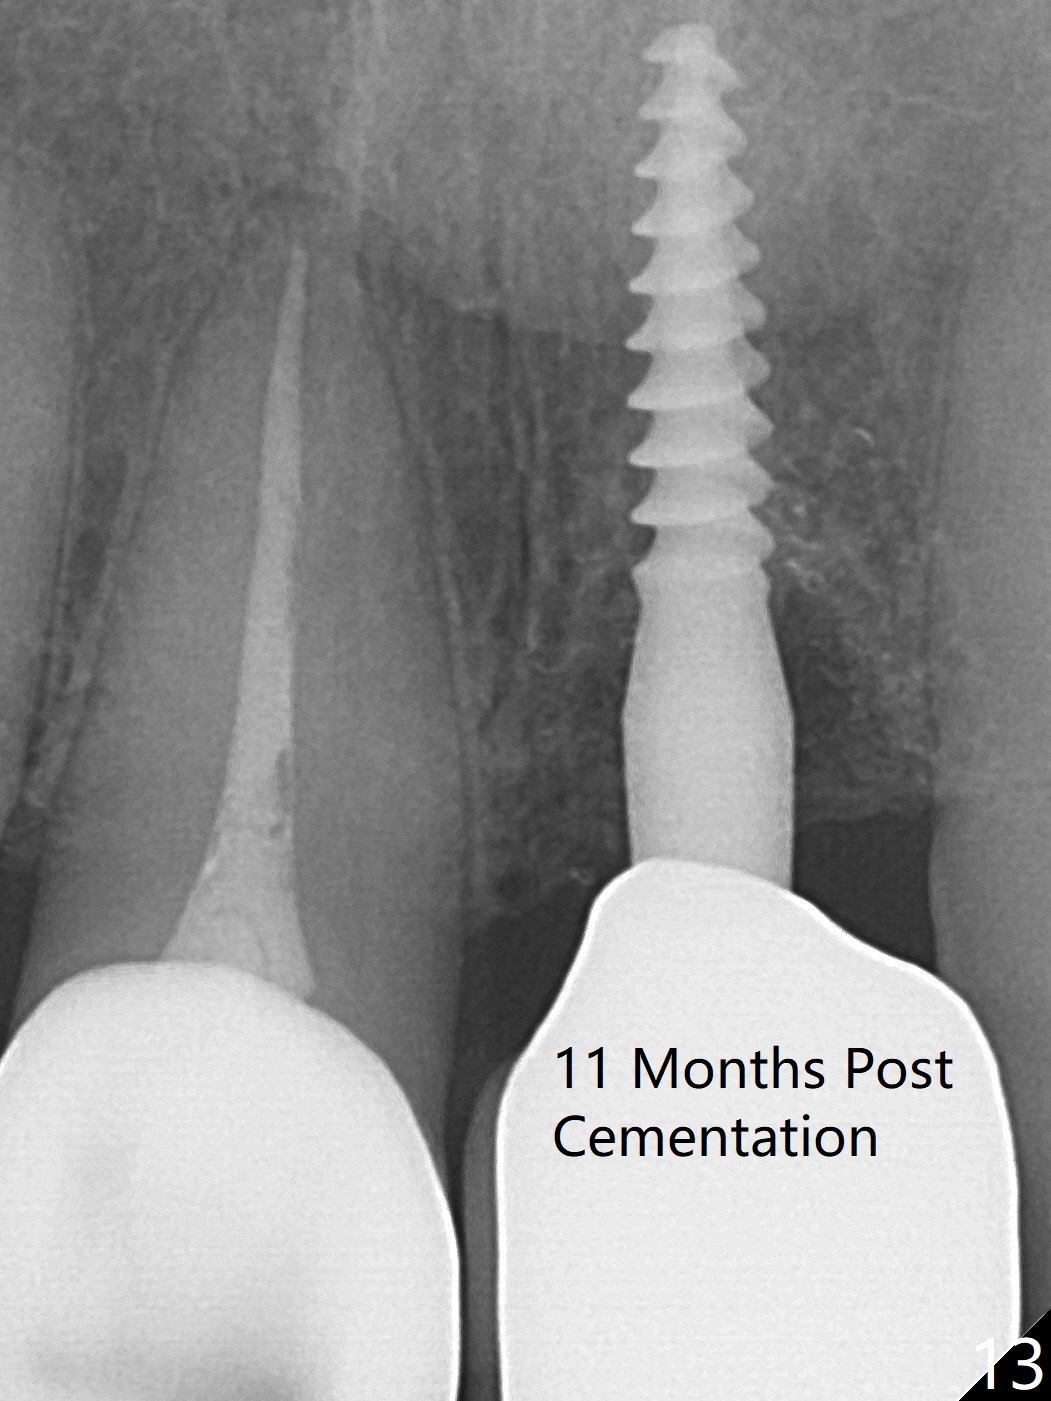

Three months postop there is no gross bone loss around the implant (Fig.10). It remains the same 5 months postop (immediately post cementation, Fig.11) and 3, 11 months post cementation (Fig.12,13).